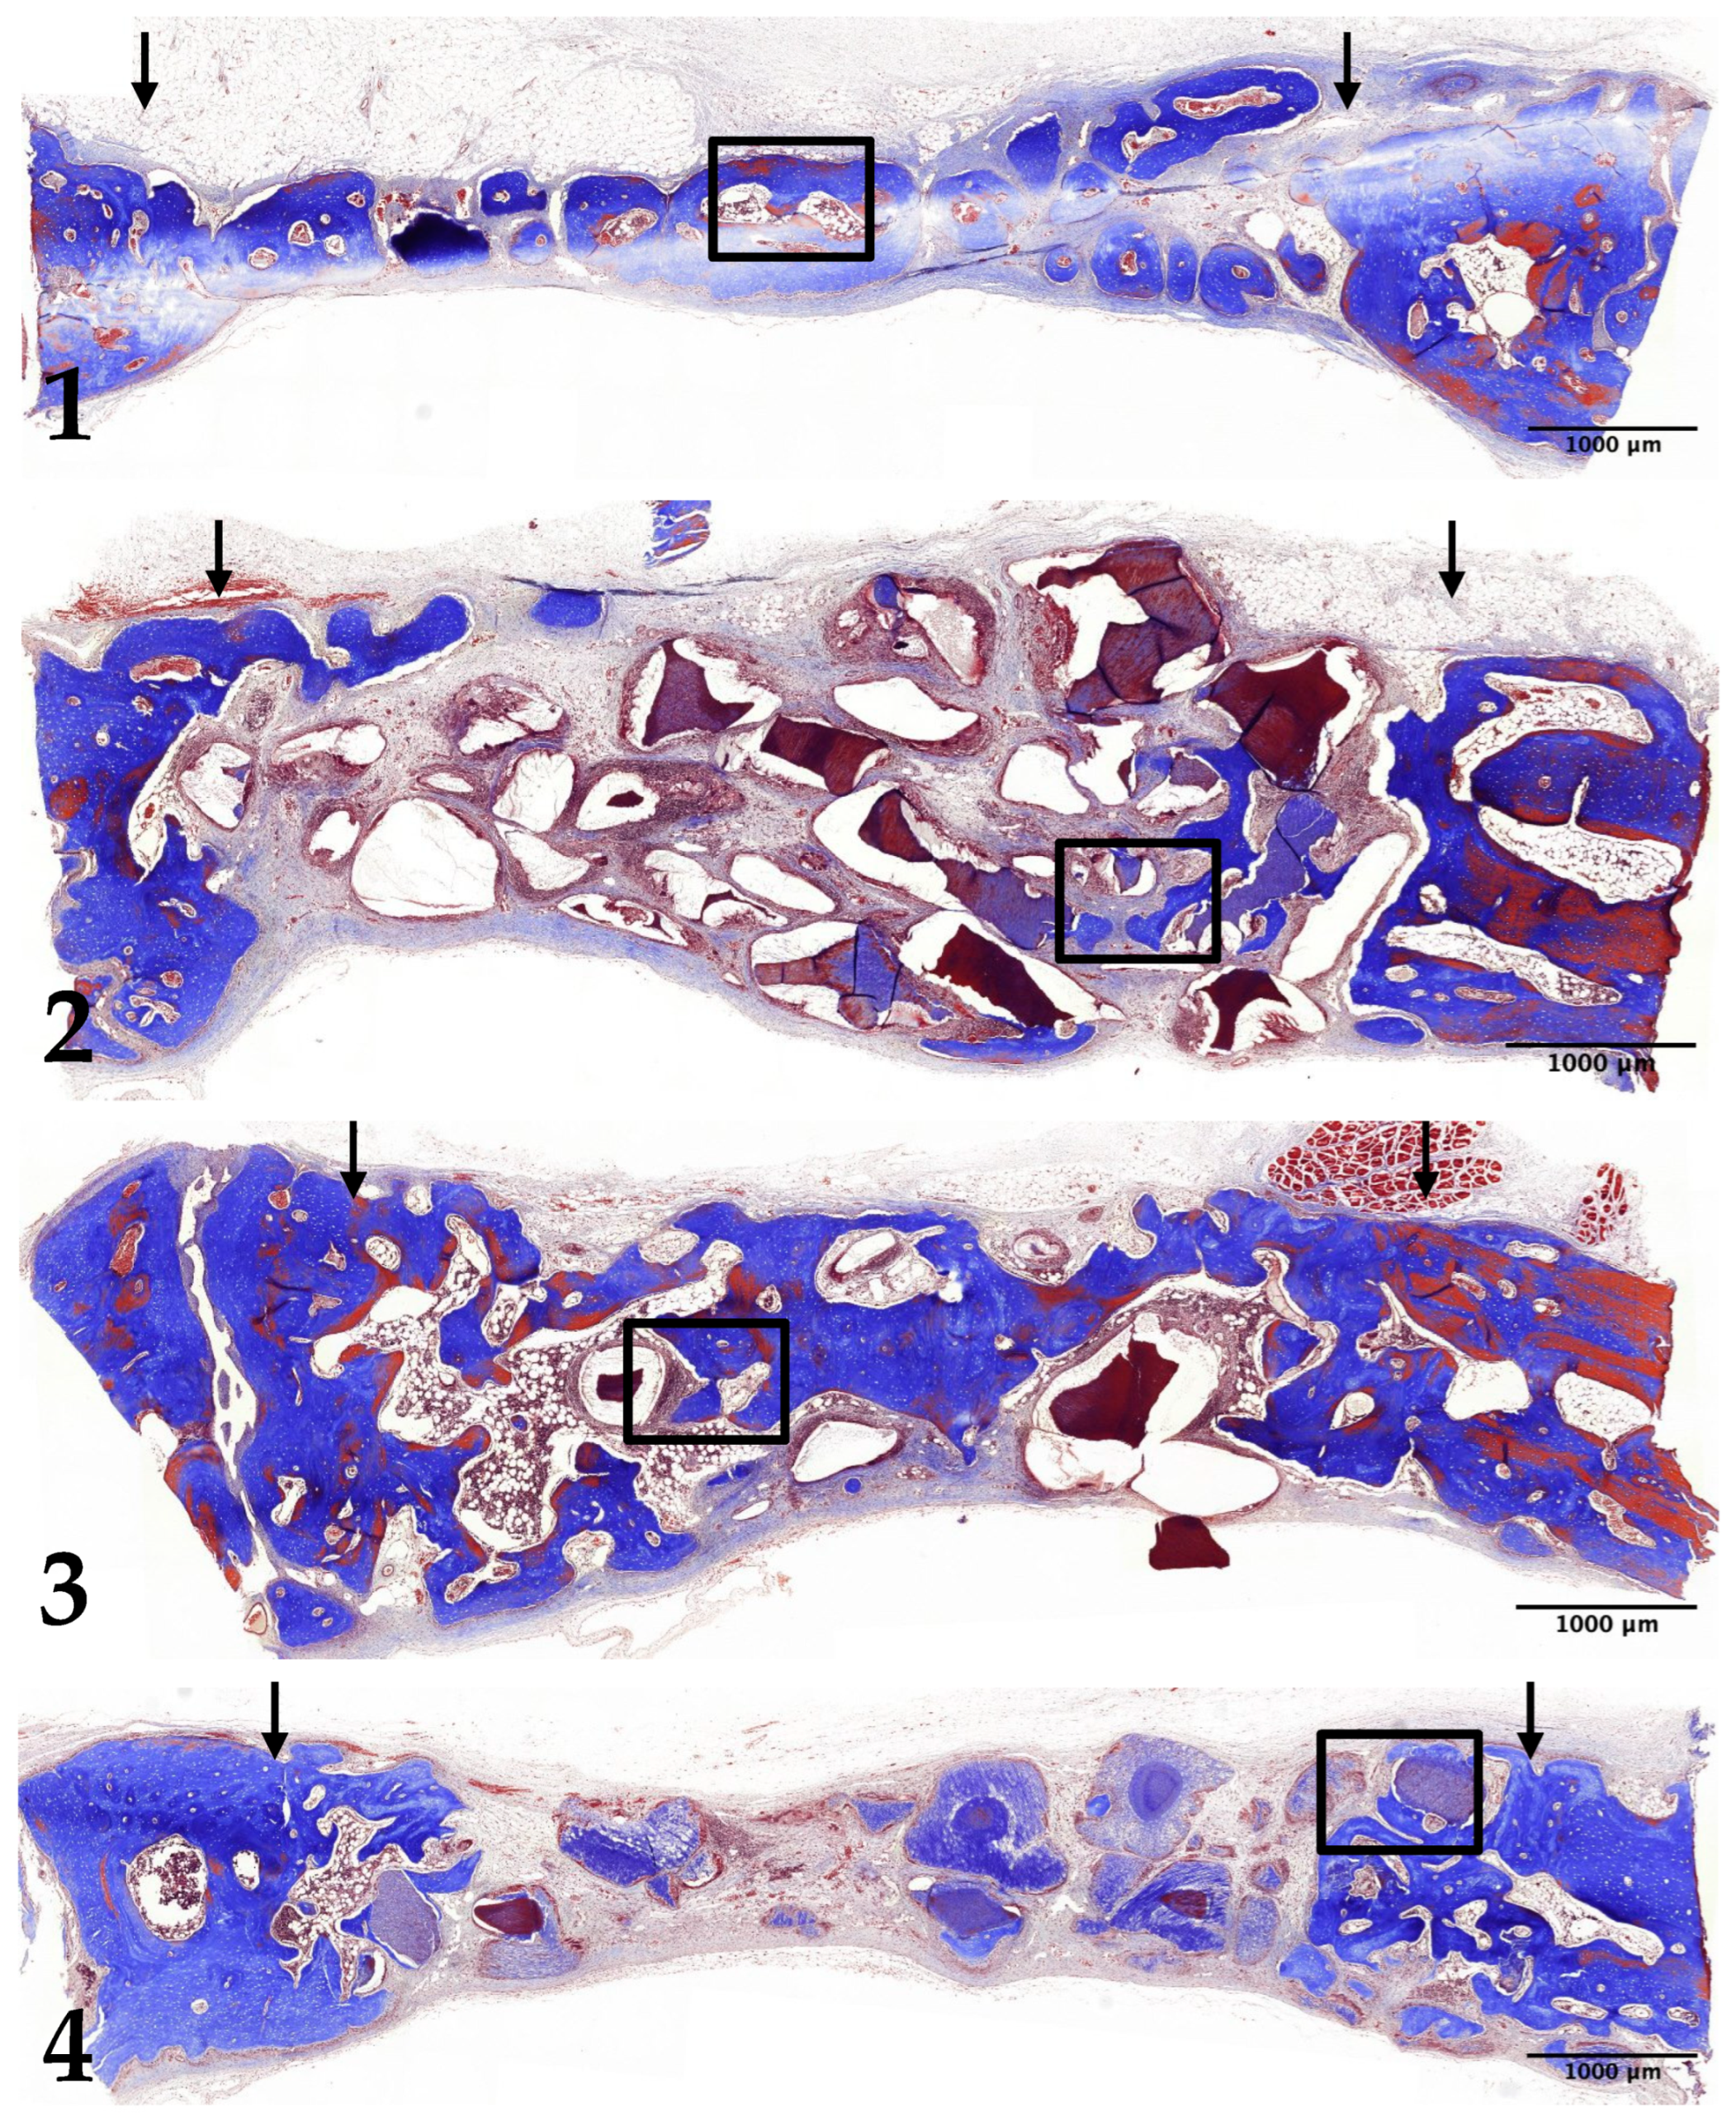

3.2. Two-Week Results

3.3. Four-Week Results

3.4. Eight-Week Results

3.5. Histomorphometric Analysis: New Bone Formation

3.6. Histomorphometric Analysis: Decrease in Remaining Graft Material Area

3.7. Histomorphometric Analysis: Quantifying Changes in Bone Marrow Area